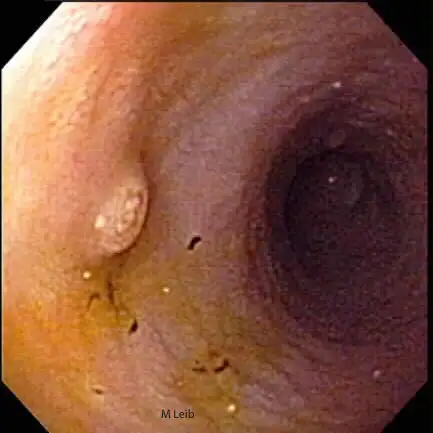

Endoscopy of the upper GI organs allows visualization of the esophagus, stomach, and proximal duodenum. This procedure can assist in the diagnosis of foreign bodies, inflammation, inflammatory bowel disease, ulcers, tumors, and strictures of the upper GI tract. It is often performed to further evaluate patients with changes in appetite, weight loss, vomiting, diarrhea, intestinal bleeding, or unexplained anemia. Recognizing normal structures and patterns of abnormal tissue can simplify biopsy sampling.

Large gastric ulcer in a 10-year-old Rottweiler. Black clotted blood is adhered to the crater of the large ulcer. The horizontal ridge is the angularis incisura; the antrum is located below the angularis.